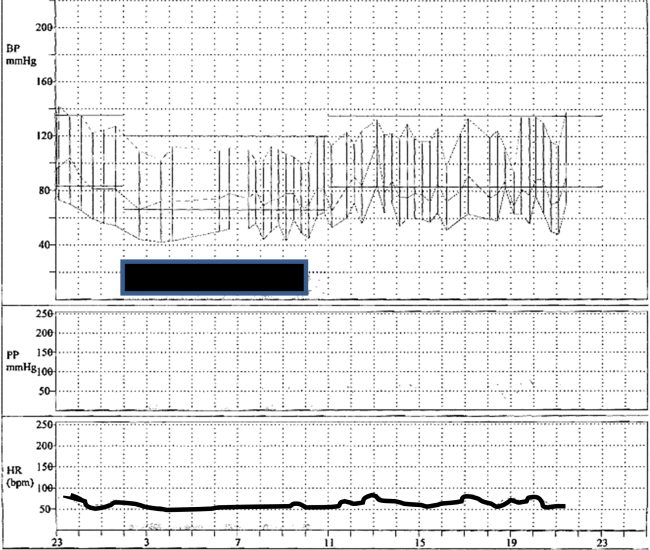

16 Year Old Example This is a 16 year old with mild unrepaired coarctation of the aorta and bicuspid aortic valve who had mean BP of 130-135 mmHg systolic and 80-85 mmHg diastolic in the right upper limb seated by repeat manual auscultation at separate visits.

This is a 16 year old with mild unrepaired coarctation of the aorta and bicuspid aortic valve who had mean BP of 130-135 mmHg systolic and 80-85 mmHg diastolic in the right upper limb seated by repeat manual auscultation at separate visits.

The patient is a wrestler and wants to play football. He admits that doctor’s visits make him nervous.

The 24-hour ABPM is shown below. Ambulatory limits of blood pressure for this study are set at 135/83 mm Hg (awake) and 120/66 mm Hg (asleep). Awake and sleep times were recorded by the patient.

Normal ABPM study indicating that this patient has white-coat hypertension. He is cleared for dynamic sports participation. However, it is still recommended that he avoid exercises such as power weight lifting and wrestling (isometric exercise).